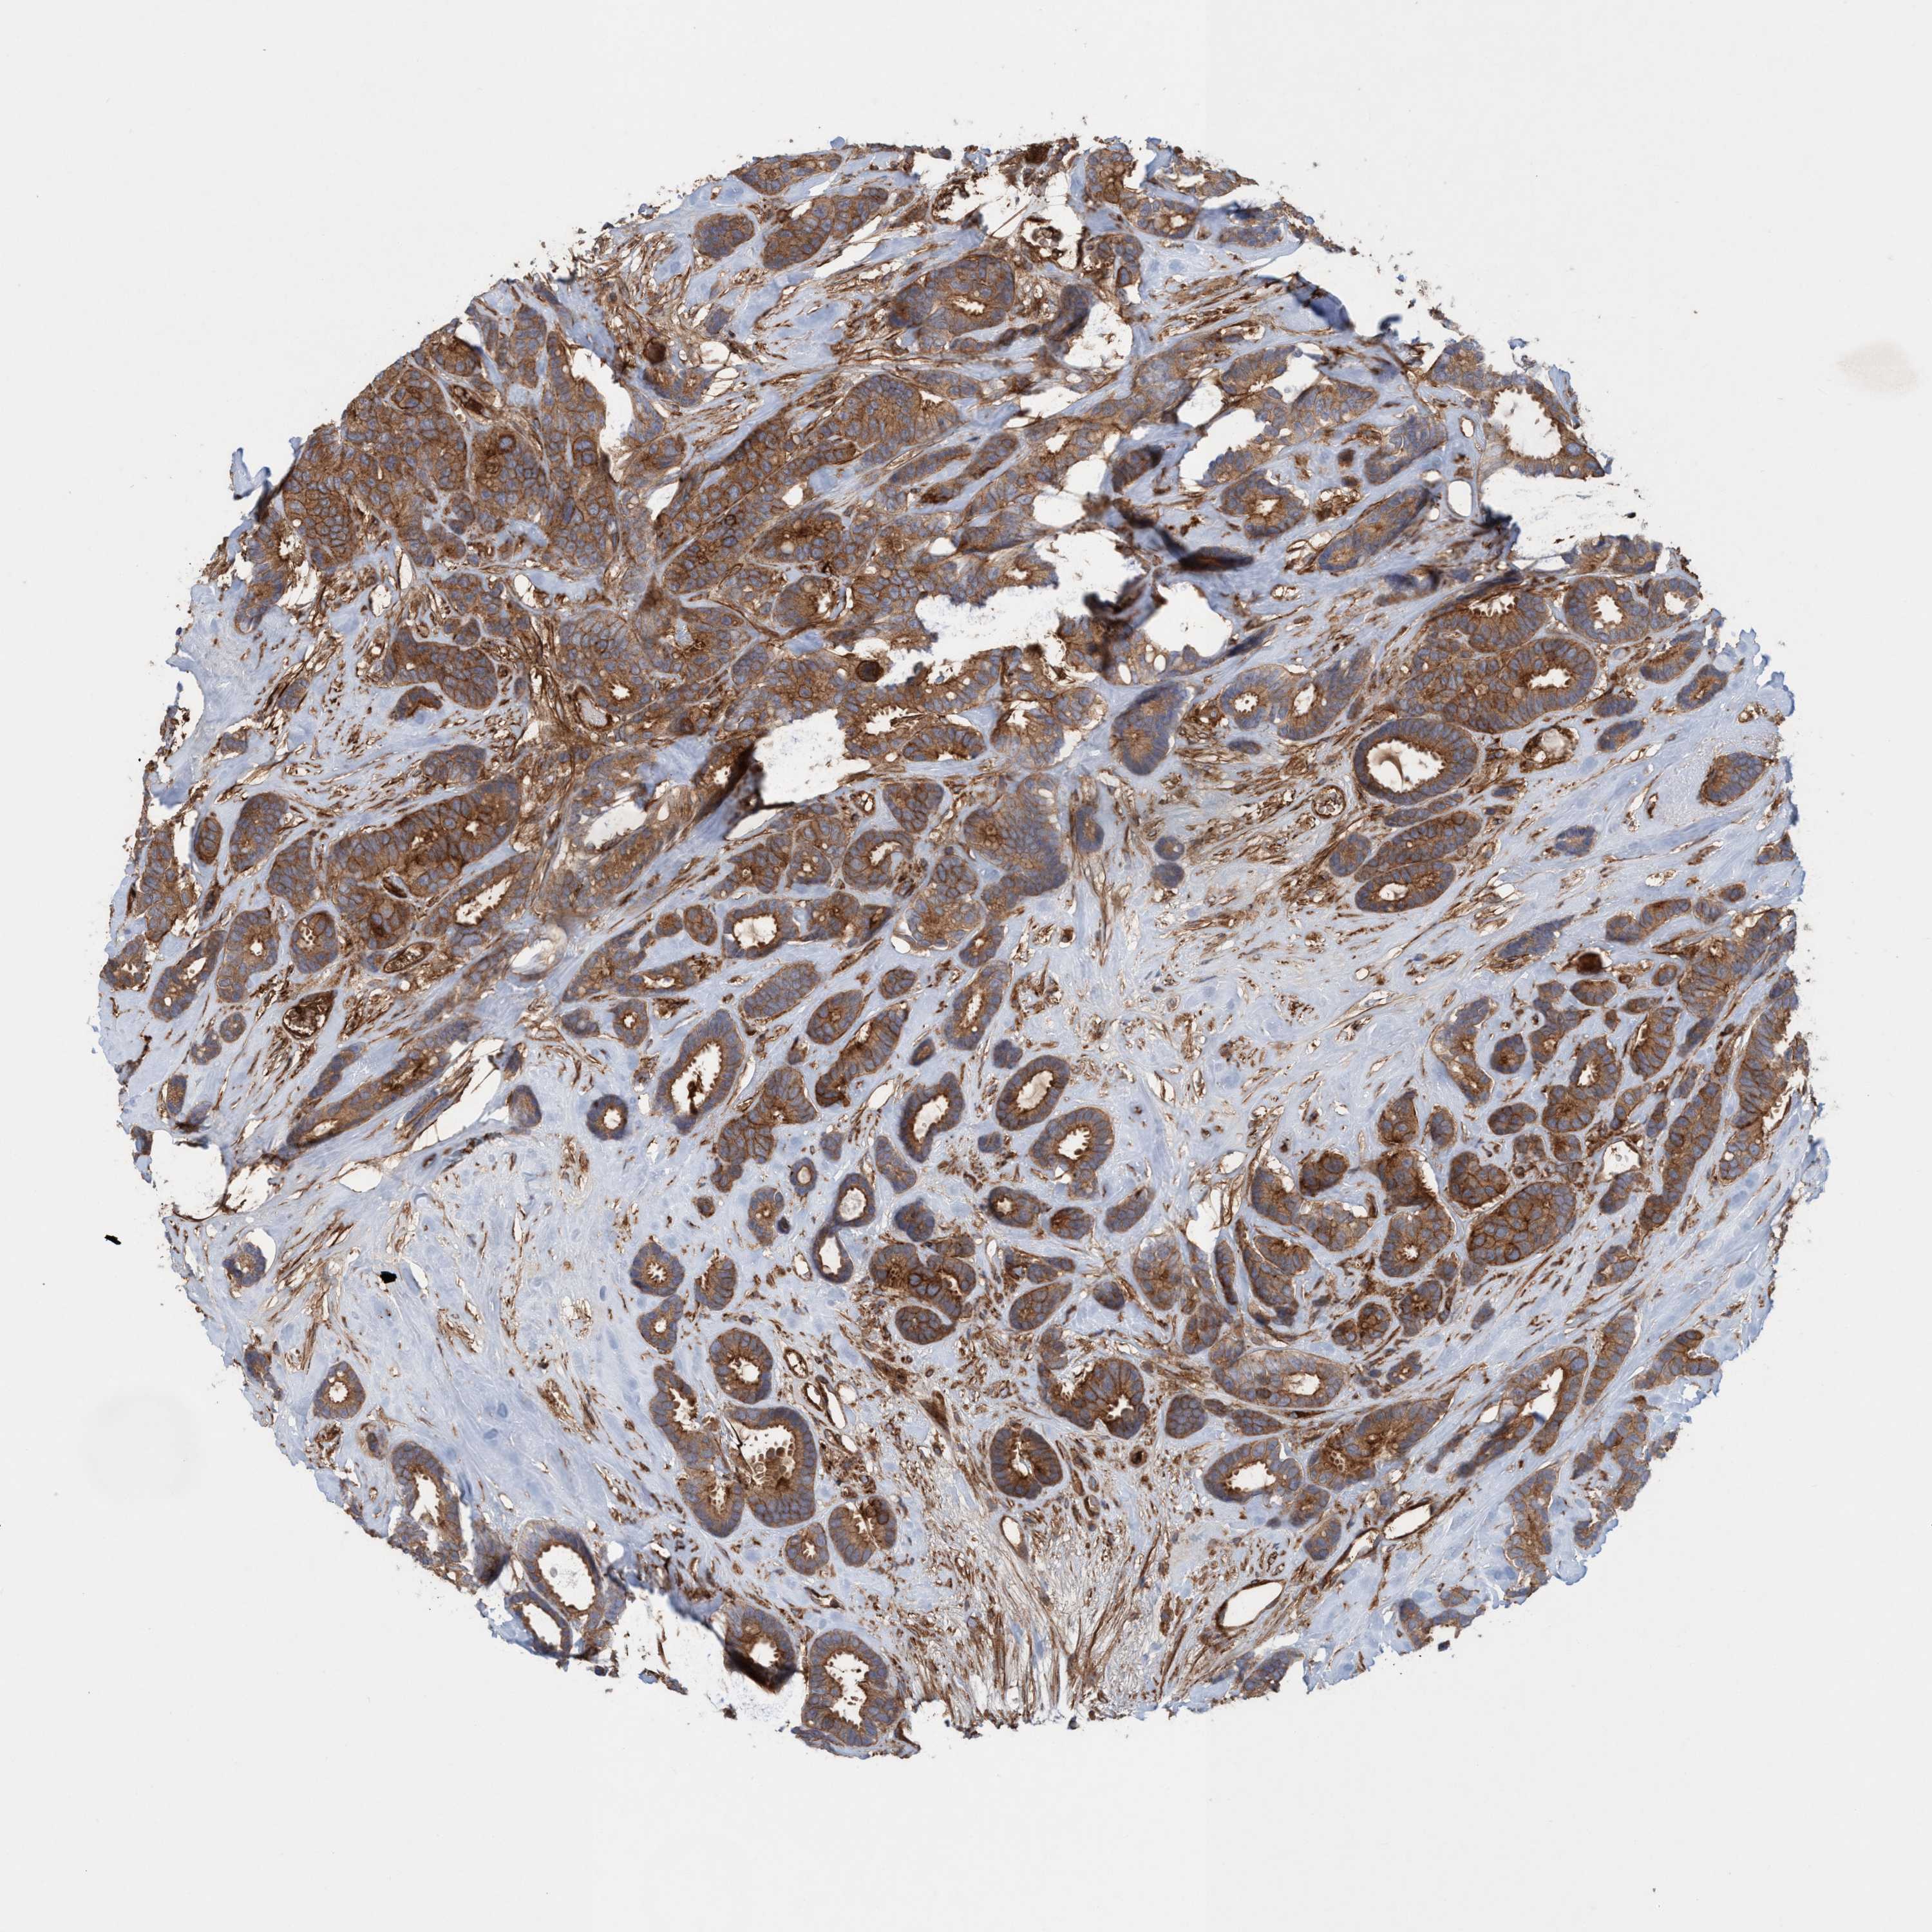

BRCA TCGA BRCA VALIDATION PROTEIN EXPRESSION

ANTIBODIES

AND

VALIDATION